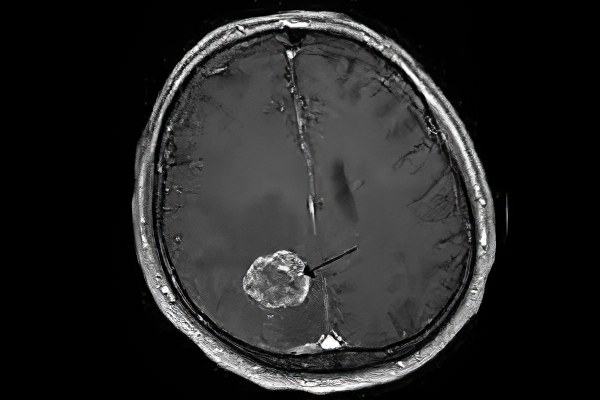

Если у вас есть один или несколько симптомов, указывающих на возможное онкологическое заболевание, важно немедленно обратиться к врачу-неврологу для обследования. Рекомендуется пройти компьютерную томографию, ультразвуковое исследование и сцинтиграфию. Наиболее информативным методом диагностики является магнитно-резонансная томография. Она позволяет определить местоположение опухоли, отслеживать динамику онкологического процесса и оценить объем пораженной области. Все перечисленные методы относятся к неинвазивным диагностическим подходам.

К инвазивным методам диагностики относятся измерение давления цереброспинальной жидкости (ликвора) и его цитологическое исследование. Также возможно проведение рентгеноконтрастной ангиографии и иммунохимического анализа. Для окончательной постановки диагноза выполняется пункционная биопсия, которая является наиболее надежным методом диагностики саркомы головного мозга.